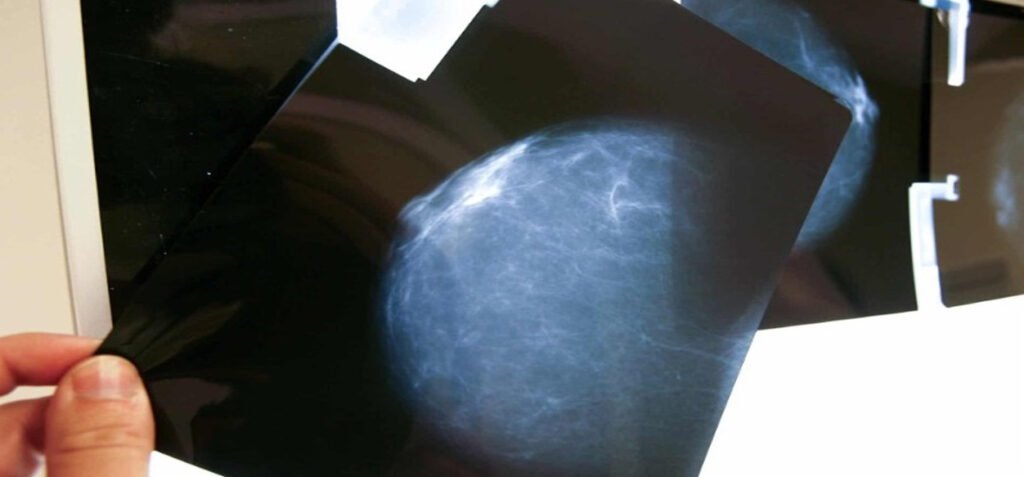

“El autoexamen no es para detectar el cáncer, sino para reconocer la normalidad del cuerpo. Las mamografías y ecografías son las que salvan vidas”, enfatizó, tras subrayar la importancia de integrar la educación sanitaria en las escuelas para crear adultos más conscientes de su salud.